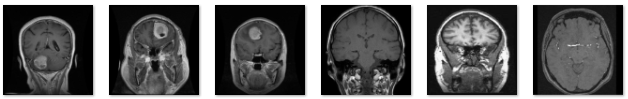

图1 样本图像

本数据集包含不同类型的脑部 MRI 影像样本:脑胶质瘤(Glioma)、脑膜瘤(Meningioma)、垂体瘤(Pituitary Tumor) 以及 正常脑部(Normal)。数据集旨在构建高精度的图像分类模型,实现对脑肿瘤与健康脑组织的自动识别与判定。通过对大量标注清晰、质量可控的MRI影像进行深度学习训练,模型能够自动提取病灶的关键结构与纹理特征,区分不同肿瘤类型并输出类别标签与置信度评分,从而为临床提供可靠的辅助诊断依据。该数据集的建立旨在推动深度学习与人工智能技术在脑肿瘤早期筛查、术前评估与智能诊断中的应用,助力实现脑部医学影像分析的标准化与智能化。